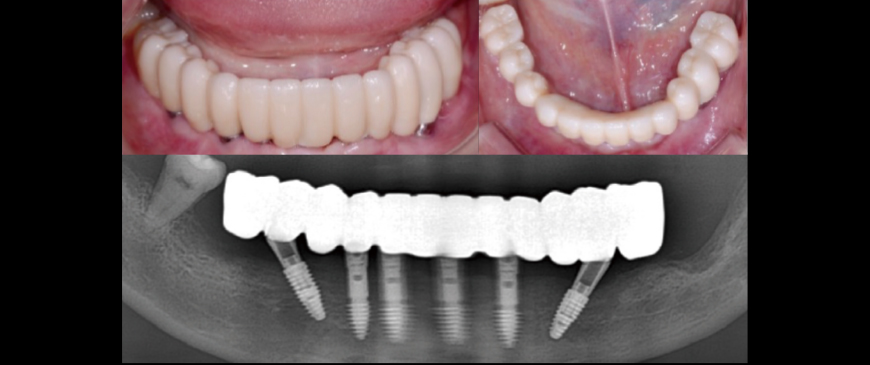

Post-surgery panoramic radiograph. Immediately after the surgery, impressions were taken to prepare provisional prostheses.

Fig 9

Post-surgery CBCT radiograph. All ARi implant threaded parts were properly positioned within the alveolar bone

Fig 10

Four days after the surgery, custom abutments and a PMMA bridge were placed.

Fig 11

Panoramic image when custom abutments and PMMA bridge were placed.

Fig 12

The final prosthesis was placed approximately 3 months later, after the soft tissue stabilized.